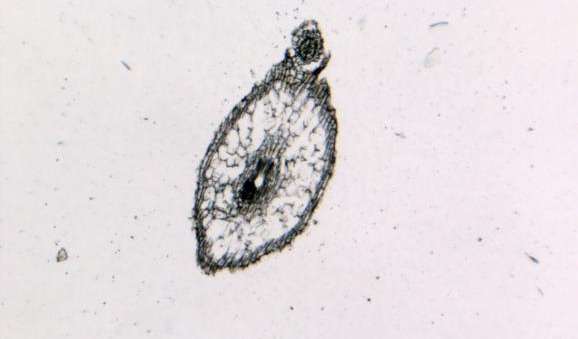

病理平臺(tái)可承接:石蠟切片,切片掃描,熒光掃描,HE染色,各種特殊染色,如:Masson、油紅O、PAS、番紅O、ALP、TRAP、甲苯胺藍(lán)以及免疫組化/熒光、原位雜交等,3D HISTECH滿足對(duì)結(jié)果高質(zhì)量,高標(biāo)準(zhǔn),周期快的實(shí)驗(yàn)外包需求,并提供染色培訓(xùn)服務(wù),分線上視頻,線下實(shí)操帶教兩種培訓(xùn)方案。

案例展示

組織染色實(shí)驗(yàn)室